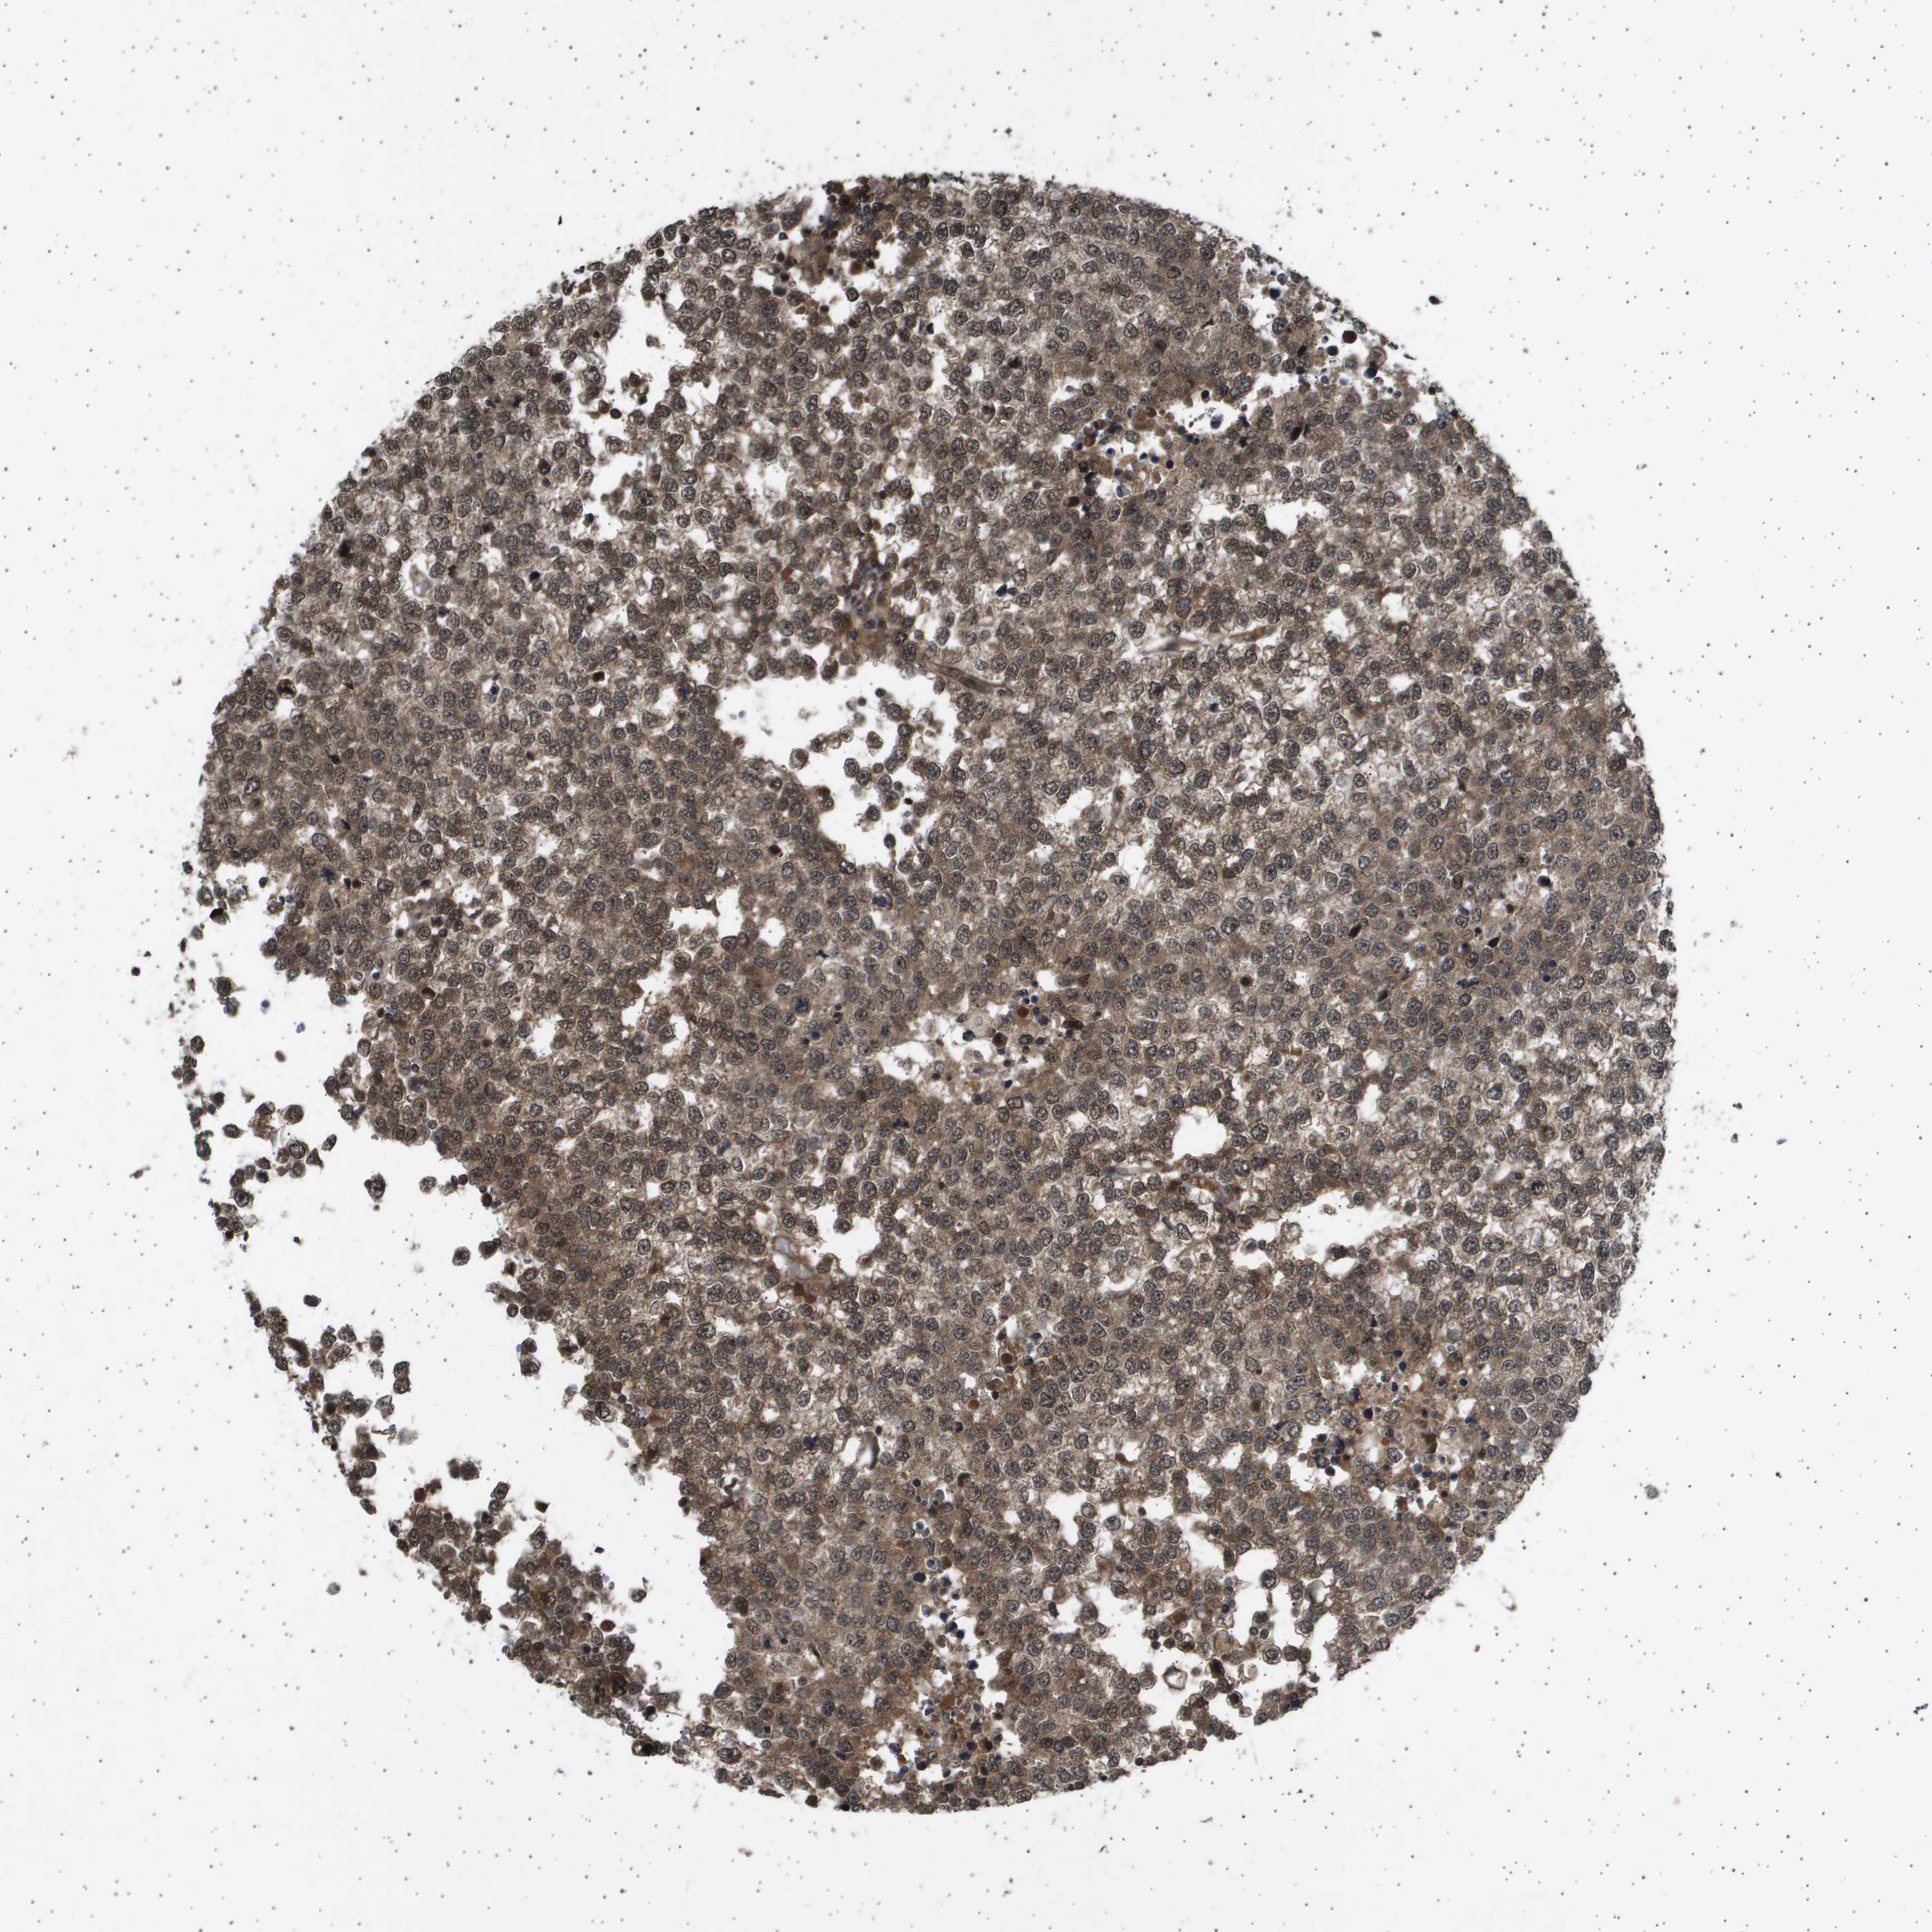

TESTIS CANCER - Protein expressioni

A mouse-over function shows sample information and annotation data. Click on an image to view it in a full screen mode. Samples can be filtered based on level of antibody staining by selecting one or several of the following categories: high, medium, low and not detected. The assay and annotation is described here.

Note that samples used for immunohistochemistry by the Human Protein Atlas do not correspond to samples in the TCGA dataset.

Antibody stainingi

Antibody staining in the annotated cell types in the current human tissue is reported as not detected, low, medium, or high, based on conventional immunohistochemistry profiling in selected tissues. This score is based on the combination of the staining intensity and fraction of stained cells.

Each image is clickable and will lead to virtual microscopy that enables deeper exploration of all samples and also displays staining intensity scores, fraction scores and subcellular localization as well as patient and tissue information for each sample.

Antibody HPA017869

Staining

High

Medium

Low

Not detected

Intensity

Strong

Moderate

Weak

Negative

Quantity

>75%

75%-25%

<25%

None

Location

Nuclear

Cytoplasmic/membranous

Cytoplasmic/membranous,nuclear

Carcinoma, Embryonal, NOS

Seminoma, NOS